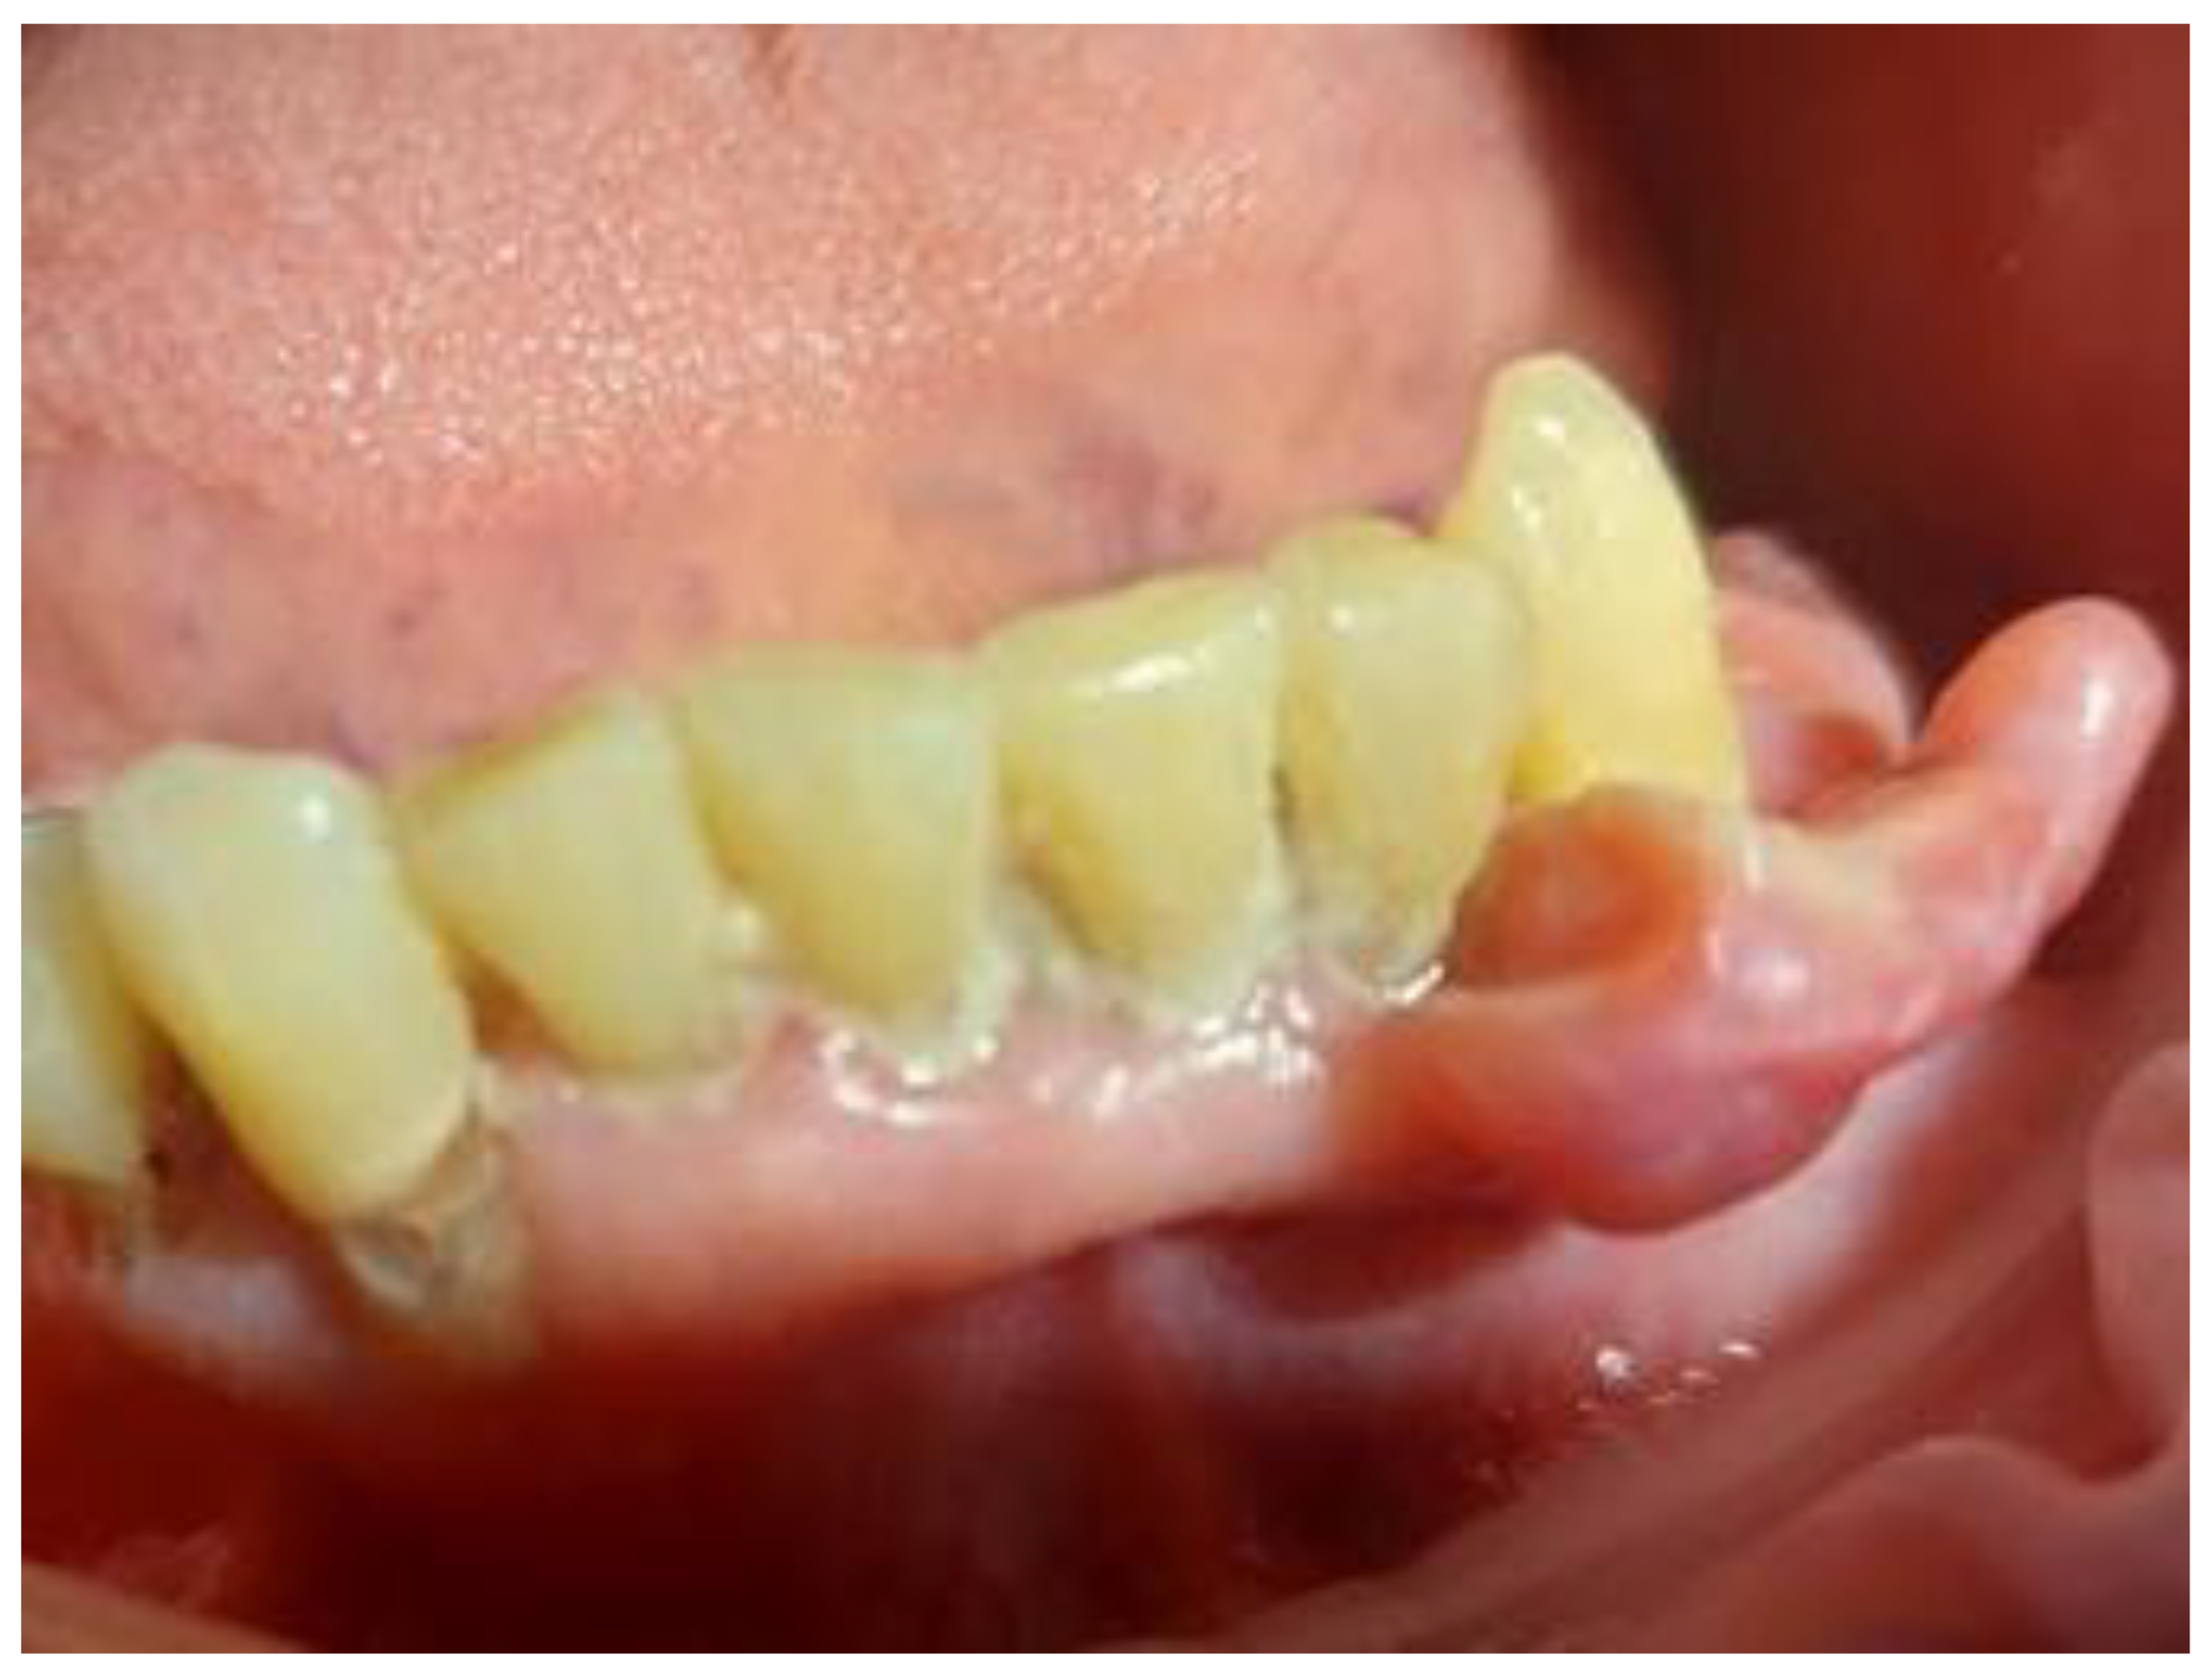

On the day of presentation to the Department of Oral Surgery, extraoral examination revealed painless, enlarged left submandibular lymph nodes. Intraorally, tumor-like gingival proliferations were observed in the regions of teeth 17–16 (22 × 10 × 5 mm) (Figure 1a) and 32–33 (30 × 20 × 6 mm), length, width, and thickness, respectively (Figure 2 and Figure 3). The lesions were pedunculated, elastic-hard, irregularly elliptical, and pink with areas of hyperemia and white spots. Both originated from marginal gingiva and were in close proximity to teeth. The patient also exhibited generalized periodontal disease with grade II mobility of teeth 17, 16, and 33. Residual roots of teeth 34, 35 were present. A panoramic radiograph showed no bony abnormalities. At this stage, the clinical appearance of the gingival lesions was suggestive of reactive hyperplastic conditions such as fibrous hyperplasia or pyogenic granuloma. However, these were considered only preliminary differential diagnoses, with the final diagnosis dependent on histopathological evaluation. The patient provided informed written consent for the proposed treatment.

Figure 1. (a) Gingival mass in the area of tooth 16. (b) One week following surgical excision of a maxillary tumor.